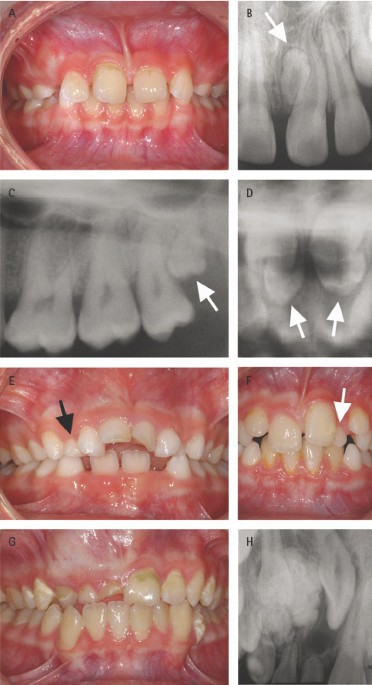

Another easy method example of charting the. Numbers 51 through 82 identify supernumerary teeth. Web Supernumerary teeth are usually discovered on images because they may interfere with normal tooth eruption Fig.